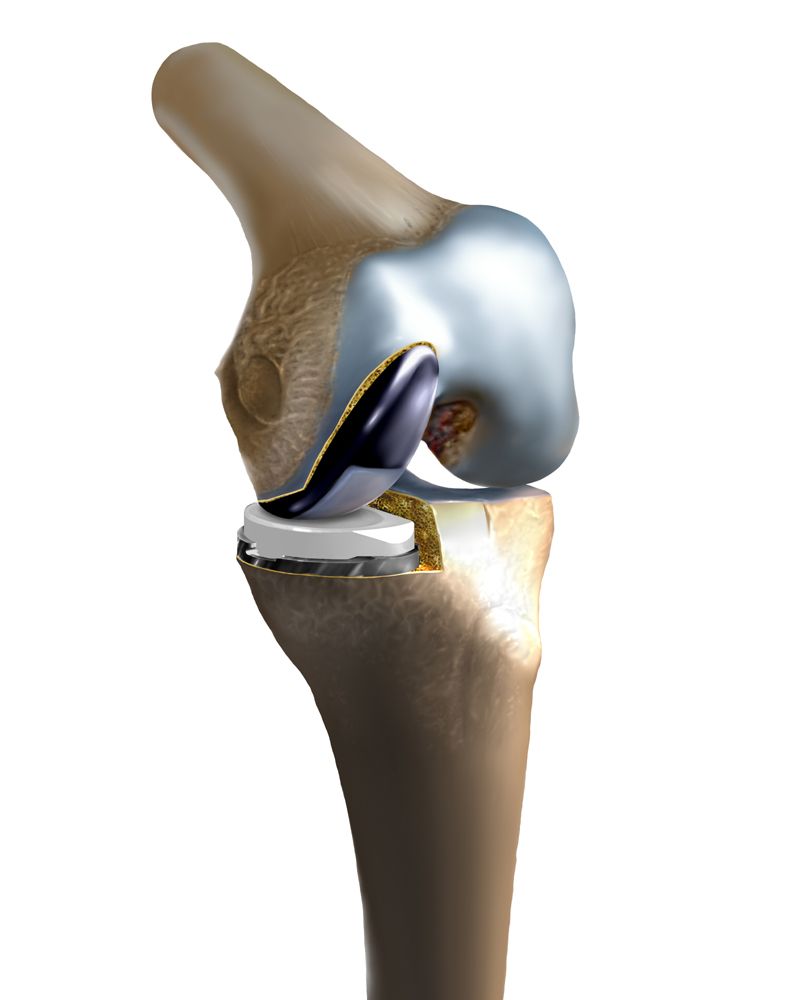

Η άρθρωση του γόνατος απαρτίζεται από τρεις ανατομικές περιοχές που σχηματίζονται μεταξύ των οστών και ονομάζονται “διαμερίσματα” (πρόσθιο-επιγονατιδομηριαίο, έσω και έξω). Η ΟΛΙΚΗ αρθροπλαστική είναι επέμβαση αντικατάστασης των φθαρμένων περιοχών- διαμερισμάτων της άρθρωσης (συνηθέστερα του έσω και του έξω). Σπανιότερα χρήζει αντικατάσταση και το επιγονατιδομηριαίο διαμέρισμα (πρόσθιο). Η ολική αρθροπλαστική αποτελεί την επέμβαση εμφύτευσης προθέσεων (δημιουργία τεχνητής άρθρωσης) με σκοπό την αποκατάσταση ανώδυνης βάδισης επαναφέροντας την ποιότητα ζωής στους ασθενείς.

Η τεχνητή άρθρωση

Οι πρώτοι τύποι εμφυτευμάτων που δημιουργήθηκαν εφάρμοσαν το σκεπτικό της κινηματικής της άρθρωσης. Περιελάμβαναν δηλαδή ένα και μοναδικό τμήμα ,συνδεδεμένο και αρθρούμενο εμφύτευμα (τύπου “μεντεσέ”). Τα νεώτερα εμφυτεύματα που χρησιμοποιούνται σήμερα σχεδιάστηκαν αναγνωρίζοντας την πολυπλοκότητα της άρθρωσης. Προσπαθούν ουσιαστικά να μιμηθούν καλύτερα την κίνηση ενός φυσιολογικού γόνατος. Σε κάποιους εξελιγμένους τύπους εμφυτευμάτων διατηρούνται οι σύνδεσμοι του ασθενούς ενώ σε κάποιους άλλους υποκαθίστανται από την πρόθεση.

Η άρθρωση του γόνατος απαρτίζεται από τρεις ανατομικές περιοχές που σχηματίζονται μεταξύ των οστών και ονομάζονται “διαμερίσματα” (πρόσθιο, έσω και έξω). Η μονοδιαμερισματική είναι επέμβαση μερικής αρθροπλαστικής της άρθρωσης του γόνατος και αφορά την αντικατάσταση του ενός τμήματος της άρθρωσης συνήθως του έσω το οποίο προσβάλλεται συχνότερα.

Οι προθέσεις αυτές είναι σχεδιασμένες να αντικαθιστούν μέρος της άρθρωσης. Αποτελεί τεχνική αρθροπλαστικής η οποία εστιάζει αποκλειστικά στο φθαρμένο τμήμα της άρθρωσης επιτυγχάνοντας την διατήρηση υγιούς τμήματος αυτής.

Η φιλοσοφία είναι παρόμοια με την ολική αρθροπλαστική ωστόσο διαφοροποιείται σημαντικά αναφορικά με την πρόσπελαση (χειρουργικό μονοπάτι) και την τεχνική τοποθέτησης των ενθεμάτων. Αποτελείται και εδώ (όπως και στην ολική ) από μεταλλικά και πλαστικά μέρη.

Τα μεταλλικά μέρη του εμφυτεύματος – πρόθεσης αποτελούνται από τιτάνιο ή κράματα κοβαλτίου – χρωμίου. Τα πλαστικά μέρη είναι κατασκευασμένα από υψηλού μοριακού βάρους πολυαιθυλένιο (Ultra high molecular weight polyethylene).

Τα μεταλλικά μέρη της άρθρωσης προσαρμόζουν στα φθαρμένα τμήματα των οστών. Το πλαστικό μέρος παρεμβάλλεται μεταξύ αυτών και είναι μικρότερο σε μέγεθος σε σύγκριση με την ολική αρθροπλαστική.

Η τεχνητή άρθρωση

Στην μονοδιαμερισματική αρθροπλαστική γόνατος, χρησιμοποιούνται προθέσεις που επικαλύπτουν τμηματικά τα άκρα του μηριαίου και της κνήμης. Στην περίπτωση που μόνο ένα διαμέρισμα (μια πλευρά) της άρθρωσης του γόνατος είναι κατεστραμμένη χρησιμοποιούνται μικρότερα εμφυτεύματα για να επικαλύψουν εκείνη την πλευρά (Μονοδιαμερισματική Αρθροπλαστική Γόνατος).